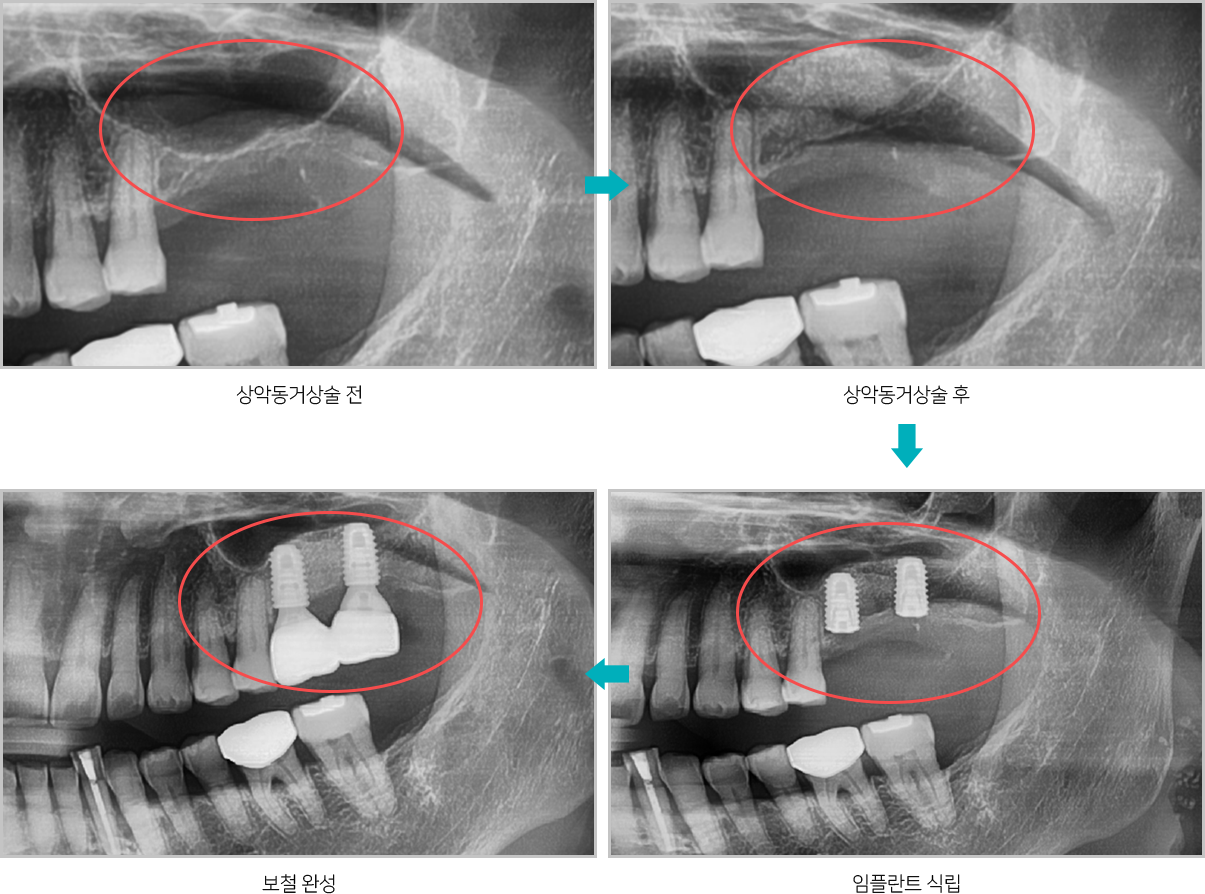

상악동거상술 전후

위턱뼈 속의 비어있는 공간을 상악동이라고 하는데

상악동과 잇몸뼈 사이에 임플란트를

심을 수 있는 만큼의

뼈가 남지 않았을 때, 잇몸뼈 위쪽에 위치한 상악동의

아래벽을 위쪽으로

들어올리고 그 공간에 뼈를 채워

넣어서 임플란트를 심을 수 있는 뼈의 양을

확보하는 술식입니다.